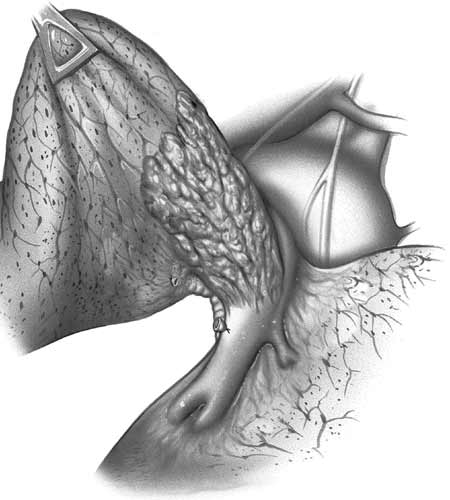

"Y"resection with lobar reimplantation

In case of upper lobe reimplantation after “Y” sleeve resection, a few technical points should be considered. The upper lobe bronchus is often so short that it is reduced to a disk of bronchial tissue where the openings of the segmental bronchi can be seen. This is more frequent on the right side (Figure 5). Also, the pulmonary artery and the lung are very close to the suture line and the exposure is poor, especially on the mediastinal side of the anastomosis (Figure 6). The anastomosis is performed in the same fashion as described above (Figure 7).

![]() |